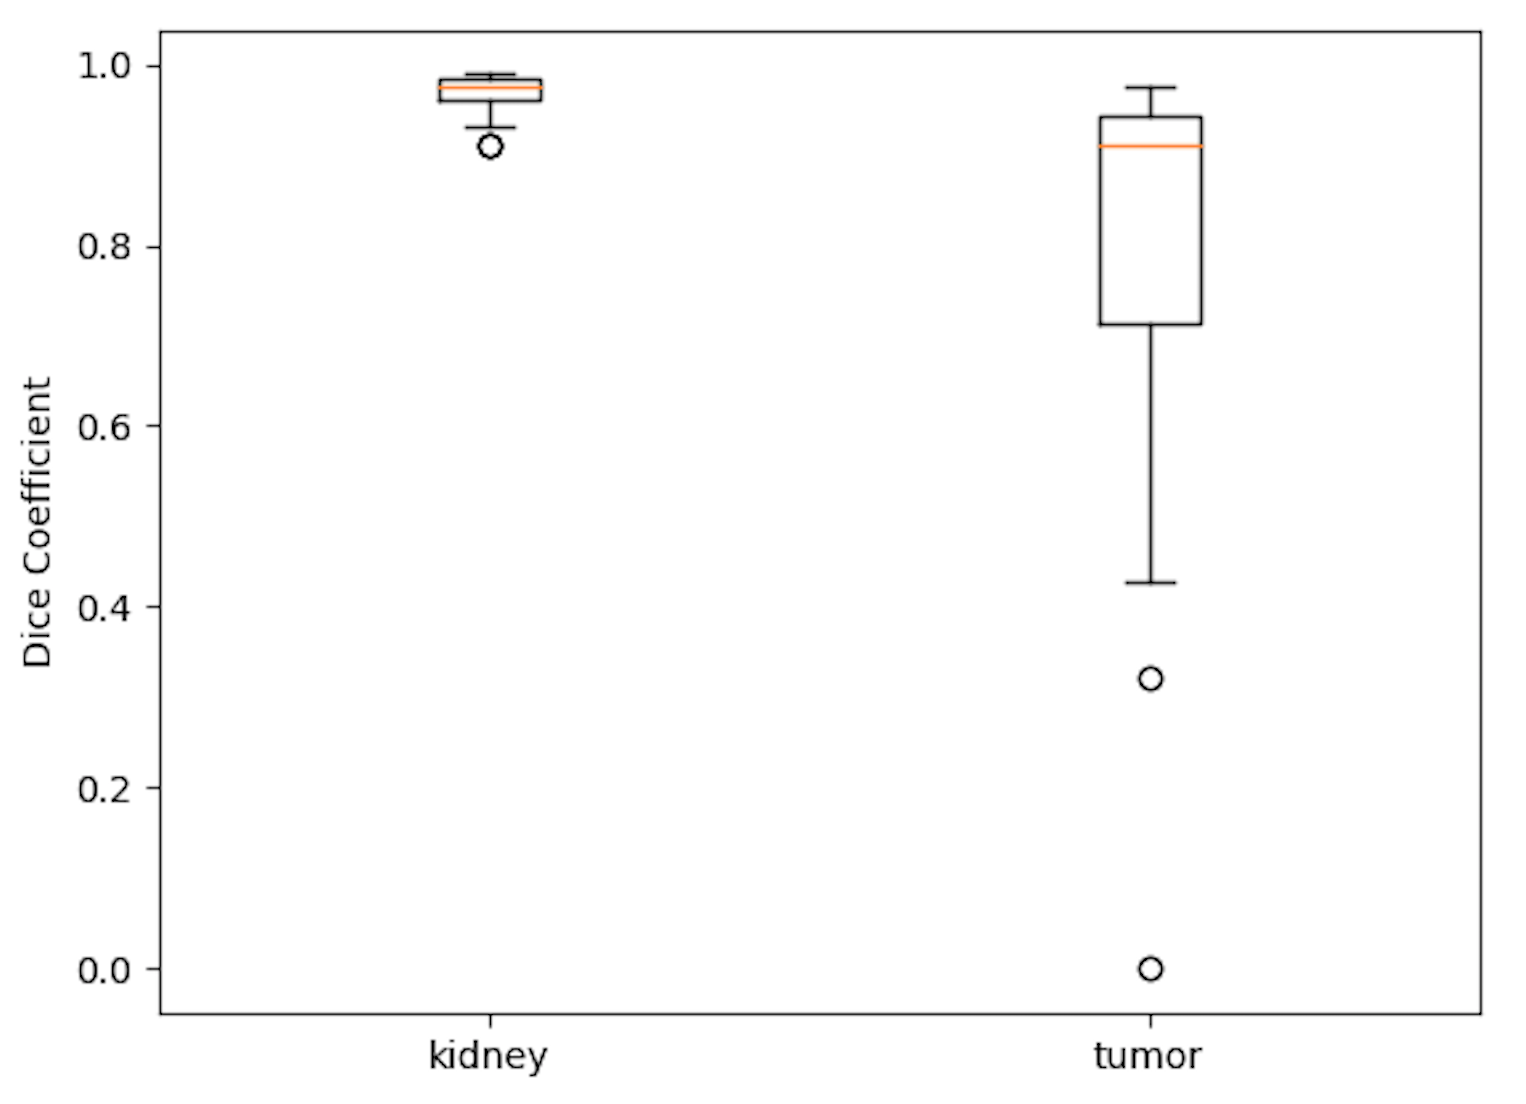

The samples of our segmentation outputs are shown in Fig.4. We observed both 2D slices from different views and 3D view to analyze the performance. Obviously, the kidney in CT images was segmented pretty well. The prediction was closely approximate the ground truth. However, some tumor was too small to get good Dice Coefficient, and also was difficult to find. Some cases with small tumor size would decrease the average Dice Coefficient drastically.

The boxplot of our test dataset is shown in Fig. 5. The average Dice Coefficient of test dataset are 0.969 and 0.805 for kidney and tumor respectively. Also, the varience of kidney is very small indicating that our algorithm is stable for kidney segmentation.